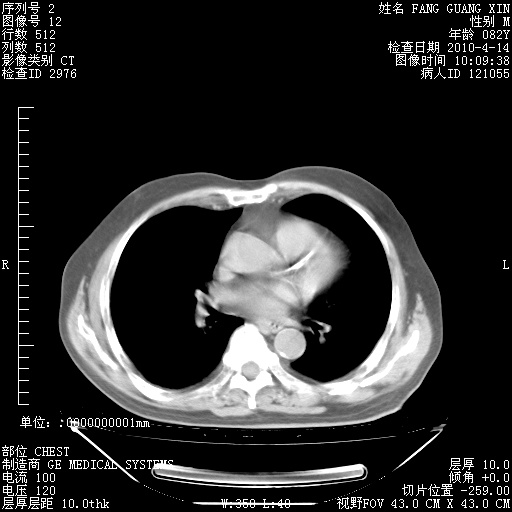

4月14日肺部CT

23.JPG

24.JPG

25.JPG

26.JPG